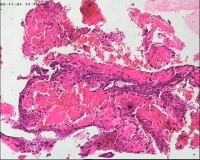

性别

女

年龄

20岁

临床诊断

一般病史

停经3月,阴道不规则流血7天。

标本名称

宫刮物

大体所见

灰白灰红碎组织一堆,大小为7*6*1cm,部分组织呈水泡状

流产残余物。

水肿的绒毛和蜕膜,没看到增生的滋养细胞。必要时可做IHC除外部分葡萄胎,并结合临床HCG。

考虑葡萄胎